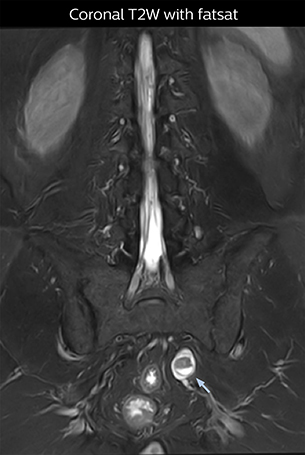

The key concept in MR neurography, Dr. Yabuki stresses, is the ability to directly visualize spinal nerves, versus inferring the presence of pathology indirectly. “Before NerveVIEW, we estimated compression of the nerve by looking for the presence or absence of fat signal on other MR images,” he says.

“For example, in sagittal images, when the presence of fat is observed in the intervertebral foramen, it suggests that there is a margin around the nerve. Similarly, the absence of fat indicates that the nerve is being compressed. So, we used to deduce nerve compression indirectly. With NerveVIEW, however, we can observe the condition of the nerves directly, regardless of the presence or absence of fat. We always prefer such direct observation of anatomy over having to make an inference about it.”

“Although symptoms of typical disc herniation and atypical hernia are very similar, the actual site of herniation is different. It is therefore important to characterize the nerve’s condition both inside and outside of the intervertebral foramina. “Conversely, if we see no abnormality in NerveVIEW, we can assume at least that there is no severe condition that requires surgery. Like this, it can help us avoid unnecessary surgery. NerveVIEW can have a tremendous impact in this way.”

“The intra-luminal signal of veins, especially around the intervertebral space, can be suppressed well with NerveVIEW. As a result, we can easily observe the detailed nerve structure around the posterior ganglion,” he says. “This is why we use 3D NerveVIEW for intraforaminal stenosis and extraforaminal stenosis/herniation (lateral disc herniation). On the other hand, if herniation is suspected to exist inside the dorsal root ganglion (DRG), balanced TFE or ProSet-FFE is applied. NerveVIEW is not suitable for evaluating the median type of herniation.” The SE-EPI DWI-based method for MR neurography works well for large FOV exams like whole-body MRI, but focal examination of nerves is often limited by the attainable spatial resolution (both inplane and slice direction) and geometric distortion. “3D NerveVIEW achieves higher in-plane resolution – close to our other routine spine sequences – and the source images can be used instead of adding a fat-suppressed T2-weighted sequence,” Tanji says.

According to Tanji, methods such as ProSet FFE, STIR or 3D VISTA are anatomically nonselective because background signals, for instance from blood vessels, often interfere with nerves, which hampers evaluation of details, especially at the peripheral side of the nerves.